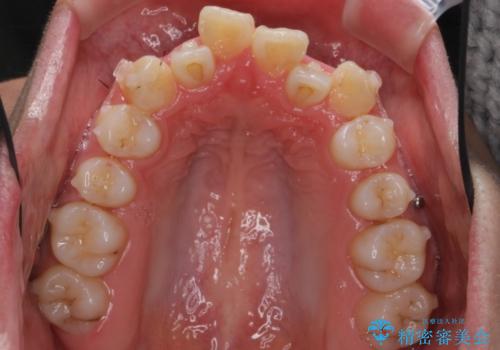

(1)口元を下げるなら、上下左右抜歯でワイヤー矯正

(2)奥歯を後ろに下げ、歯並びを拡大し、歯を少し削って抜かずにインビザライン矯正 矯正用ミニスクリュー併用 口元は下がらない

リファインメントもなく、1回で治療が終了しました。大変うまくいったケースです。

主治医としては、前歯の並びをもう少しこだわりたかったのですが、満足度が高く、リファインメントは希望されませんでした。

八重歯も重症でなければインビザラインでも並びを歯を抜かずに整えることができます。